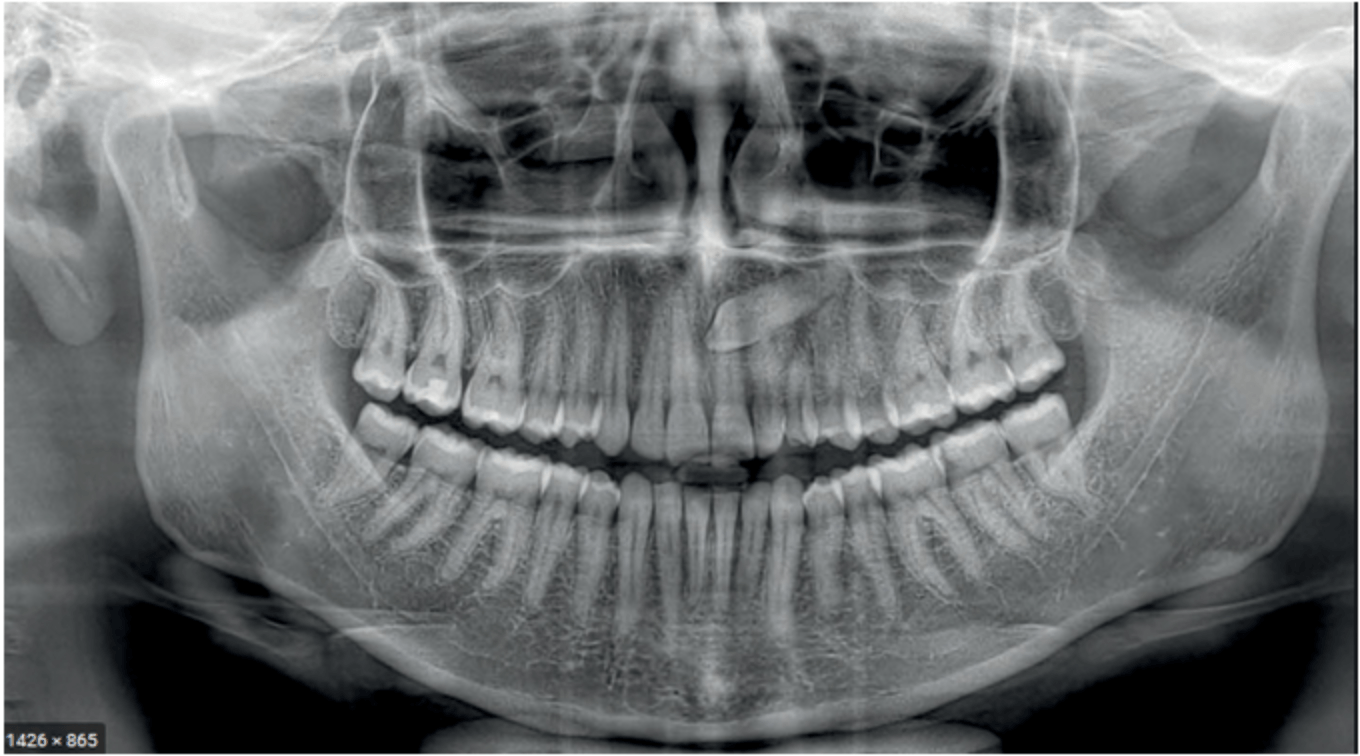

Žandikaulių skaitmeninės rentgeno nuotraukos (Ortopantomogramos)

Panoraminė nuotrauka (Ortopantomograma)

Ši nuotrauka apima ne vieną lokalią sritį,

o bendrą viršutinio ir apatinio žandikaulio vaizdą,

todėl yra tinkama planuojant didelės apimties gydymą.